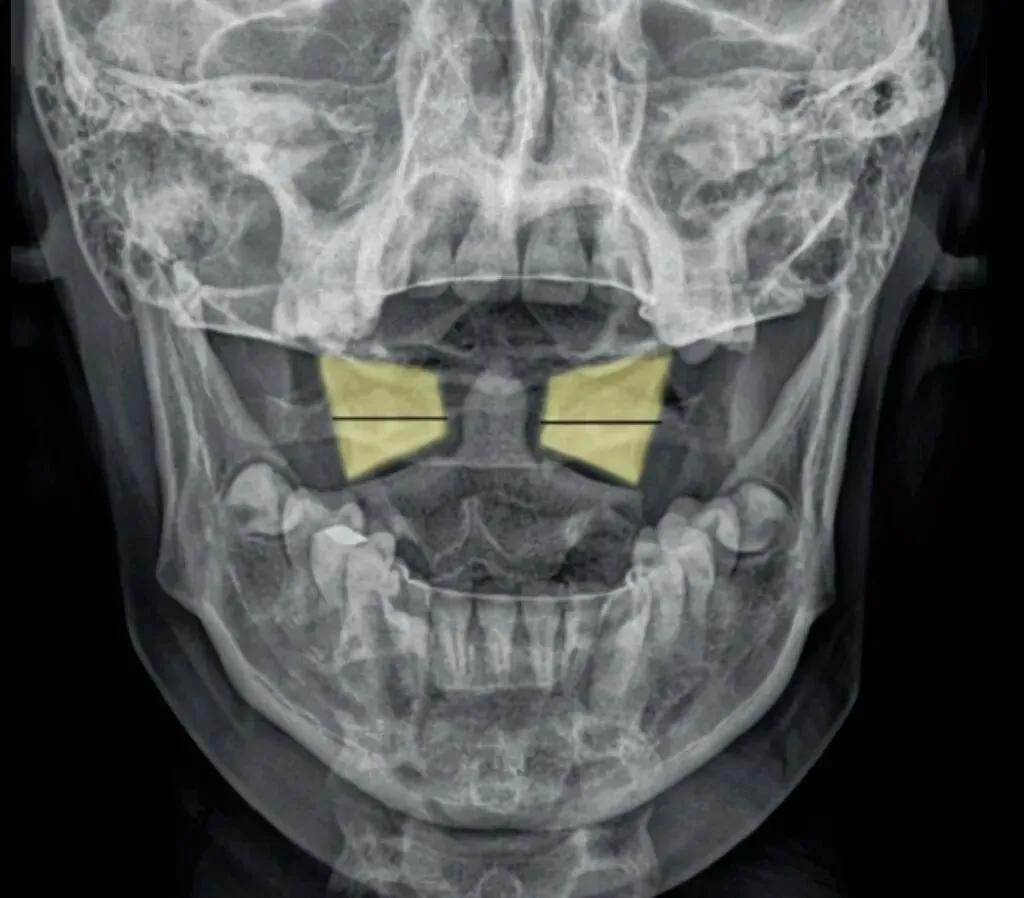

十张口是指寰枢椎的结构和位置关系,我们主要观察寰齿间隙和寰枢关节间隙及寰椎侧块的大小,来判断寰枢关节有无脱位的情况。

首先是寰齿间隙,如果枢椎与颈三的棘突位于同一条直线,

那么寰齿间隙哪边宽,就代表寰椎向哪边发生了侧方移位。

如果不在一条直线上,那就代表枢椎也有侧向的移动或旋转。

接下来是寰枢关节间隙,也称寰枢外侧关节,主要看两侧间隙是否等大,

如果一边宽一边窄,就代表寰椎向窄的一方发生了侧向倾斜。

再下来看寰椎侧块的大小,正常情况下侧块两边的宽度是等大的,

如果哪边侧块变大,就代表哪边的侧块向前方发生了旋转。